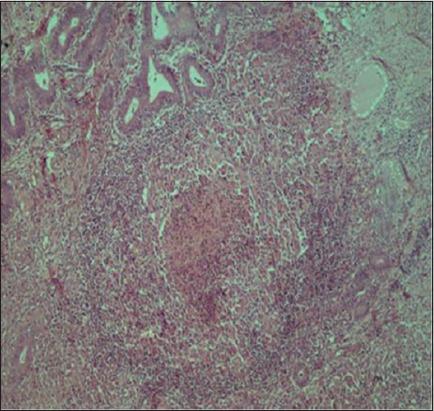

In studied female genitalia, 108 (16.30%) showed gross abnormalities with overall 23.32% occurrence of pathological conditions (macroscopic and microscopic lesions). Pathological involvement of the uterus was the highest 68 (62.96%), followed by the ovaries 27 (25%) and other organs. Major uterine condition observed was endometritis (5.60%). In uterine infections, 35 (5.30%) samples were found positive for spp., 12 (1.81%) samples for , and 3 (0.45%) samples were positive for spp. Among the samples positive for by PCR, 3 were found positive by IHC also. was detected by PCR using specific primers in a case of hydrosalpinx. It was concluded that many pathological lesions in female genitalia of functional significance play a major role in infertility in goats.

在所研究的雌性生殖器中,108个(16.30%)出现肉眼可见异常,病理状况(宏观和微观病变)的总体发生率为23.32%。子宫的病理累及率最高,为68个(62.96%),其次是卵巢,为27个(25%),其他器官。观察到的主要子宫病症是子宫内膜炎(5.60%)。在子宫感染中,35个(5.30%)样本检测出[具体病原体1]属阳性,12个(1.81%)样本检测出[具体病原体2]阳性,3个(0.45%)样本检测出[具体病原体3]属阳性。在PCR检测为[具体病原体1]阳性的样本中,有3个通过IHC检测也呈阳性。在一例输卵管积水病例中,使用特异性引物通过PCR检测到了[具体病原体4]。得出的结论是,雌性生殖器中许多具有功能意义的病理病变在山羊不育中起主要作用。